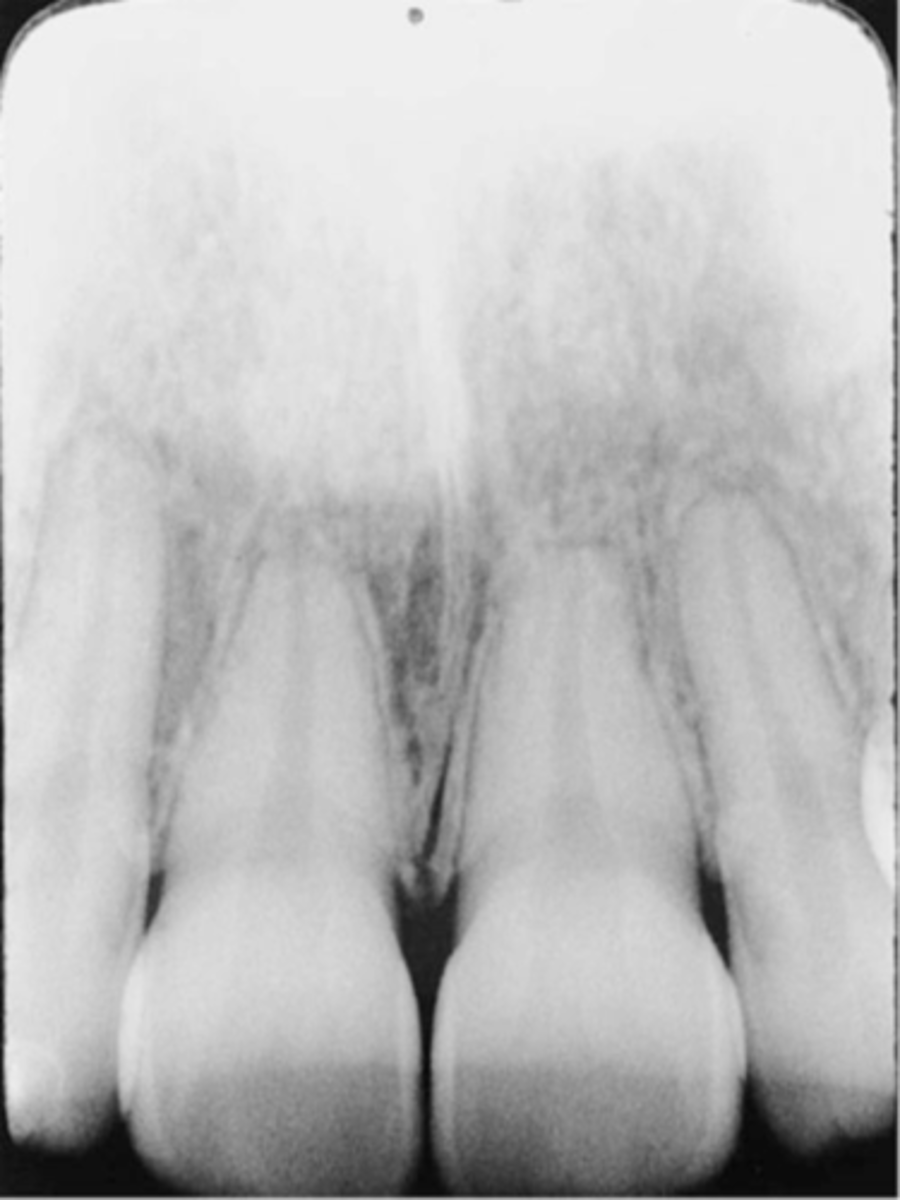

Reversed Film

-Light images with a herringbone pattern are seen

-Film was placed in the mouth backward/reversed and then exposed

-To avoid always note the front and back sides of the film before placing it in the patient's mouth

Image Receptor-->Reversed Film Image Error (Herringbone error)

Cause - The image receptor film packet positioned backward - embossed lead foil pattern as an artifact

-Putting film or phosphor plate sensor in backwards causes mirror image and image to be less distinct.

Correction - Determine the front side (tube side) of the film packet prior to placing into the image holder.

Reversed film with a herringbone/tire track pattern